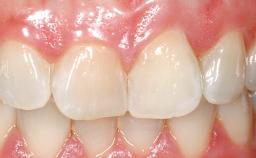

Immediate Flapless Placement of an Implant in a Maxillary Left Central Incisor Site

A 42-year-old female patient was referred to our clinic at the School of Dentistry of the University of São Paulo in November 2004, presenting a deficient restoration in the upper left central incisor. The clinical examination revealed no gingival retraction or any signs of gingival inflammation and, therefore, previous periodontal treatment was not considered. The patient presented a high lip line at full smile and a thin tissue biotype. This combination characterized a high-risk situation from an anatomic point of view, which required careful preoperative planning and cautious surgical execution.

| Soft Tissue Contour and Volume | Ideal |